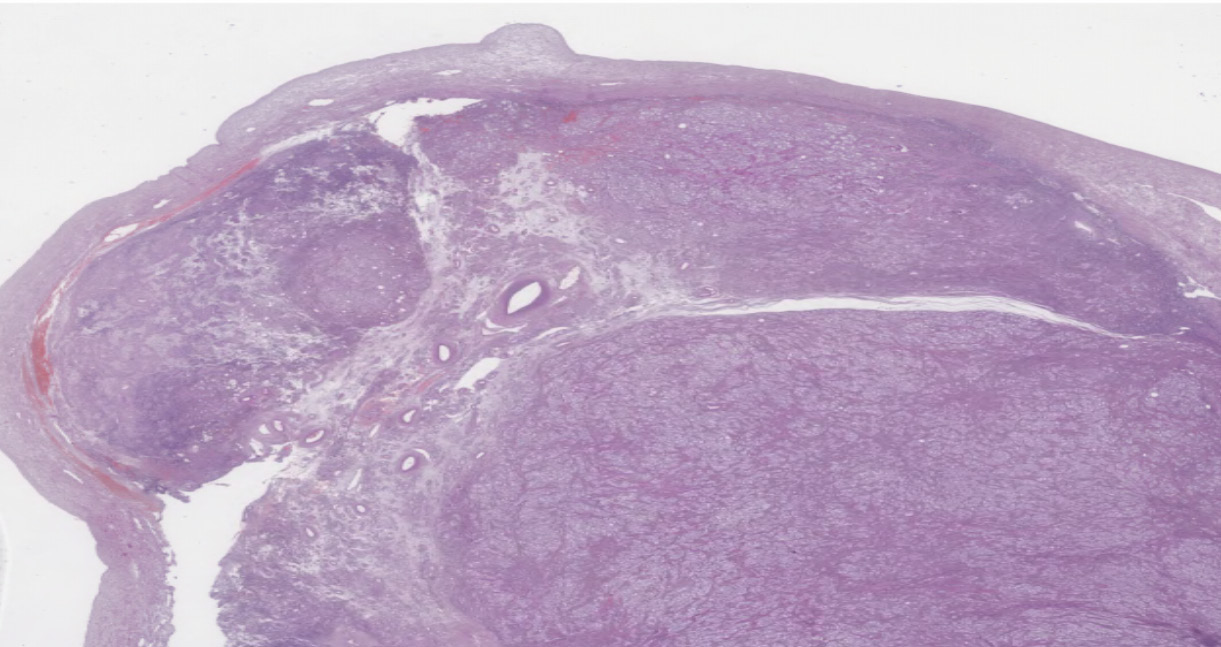

A histological examination of the excised appendages (see Fig. 2–9) revealed the concurrent presence of ovarian stroma and testicular tissue, consisting of tubules lined with Sertoli cells devoid of atypia and spermatogenesis, surrounded by Leydig cells. This finding suggests the presence of bilateral ovotestes. Fallopian tubes exhibited signs of hypoplasia, manifesting as a polycystic mass lined by a single layer of flattened tubal epithelium.

Fig. 2. Right uterine adnexa. Fragments of the ovotestis composed predominantly of testicular tissue (A) with a lobulated structure and ovarian stroma (B), enclosed within a thick tunica albuginea (C). Hematoxylin and eosin staining, ×800

Fig. 5. Right fallopian tube with features of hypoplasia, presenting as a polycystic structure lined by a single layer of flattened tubal epithelium. Hematoxylin and eosin staining, ×6

Fig. 6. Left uterine adnexa. Fragments of the ovotestis consisting predominantly of lobulated testicular tissue and ovarian stroma, enclosed within a thick tunica albuginea. Hematoxylin and eosin staining, ×6

Fig. 9. Left fallopian tube with features of hypoplasia, presenting as a cystic structure lined by a single-layered tubal epithelium with occasional epithelial projections. Hematoxylin and eosin staining, ×200, ×60